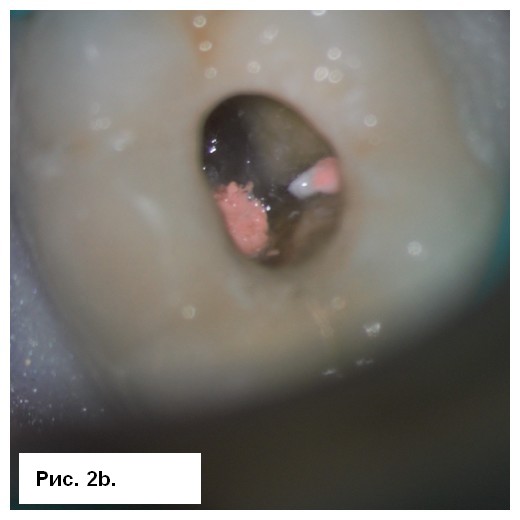

Симптоматика исчезла в последующие несколько дней. Второе посещение было проведено через 3 нед. Со слов пациента, зуб был асимптоматичным. После изоляции корневые каналы были вскрыты, проведена эвакуация гидроксида кальция. Затем каналы обтурировали биокерамическим силером BioRoot RCS (Septodont) методом одного штифта (рис. 2b) и выполнено композитное восстановление (рис. 2с). Была сделана послеоперационная радиография (рис. 3а), пациент записан на регулярные осмотры.